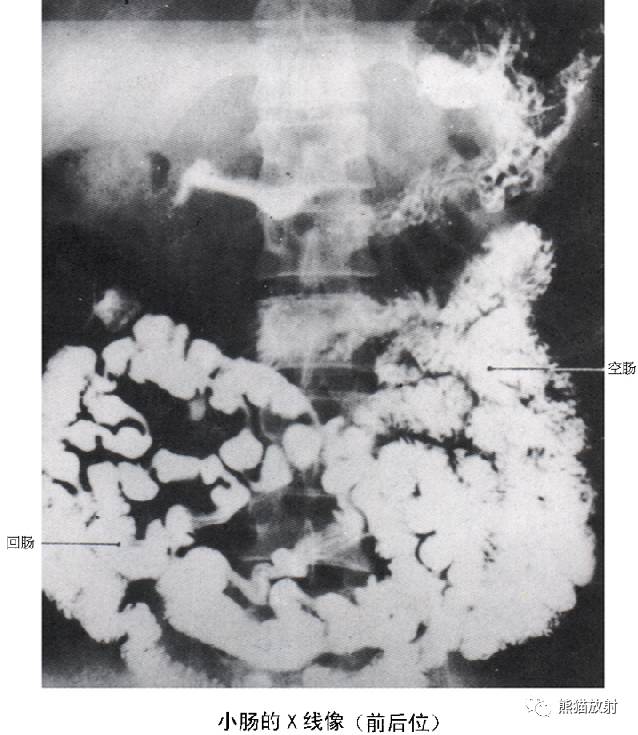

8 Small Bowel 小肠

1 Jejunum 空肠,2 Junction of the ileum and jejunum 回肠和空肠的连接部,3 Ileum 回肠,4 Cecum 盲肠,5 Appendix 阑尾